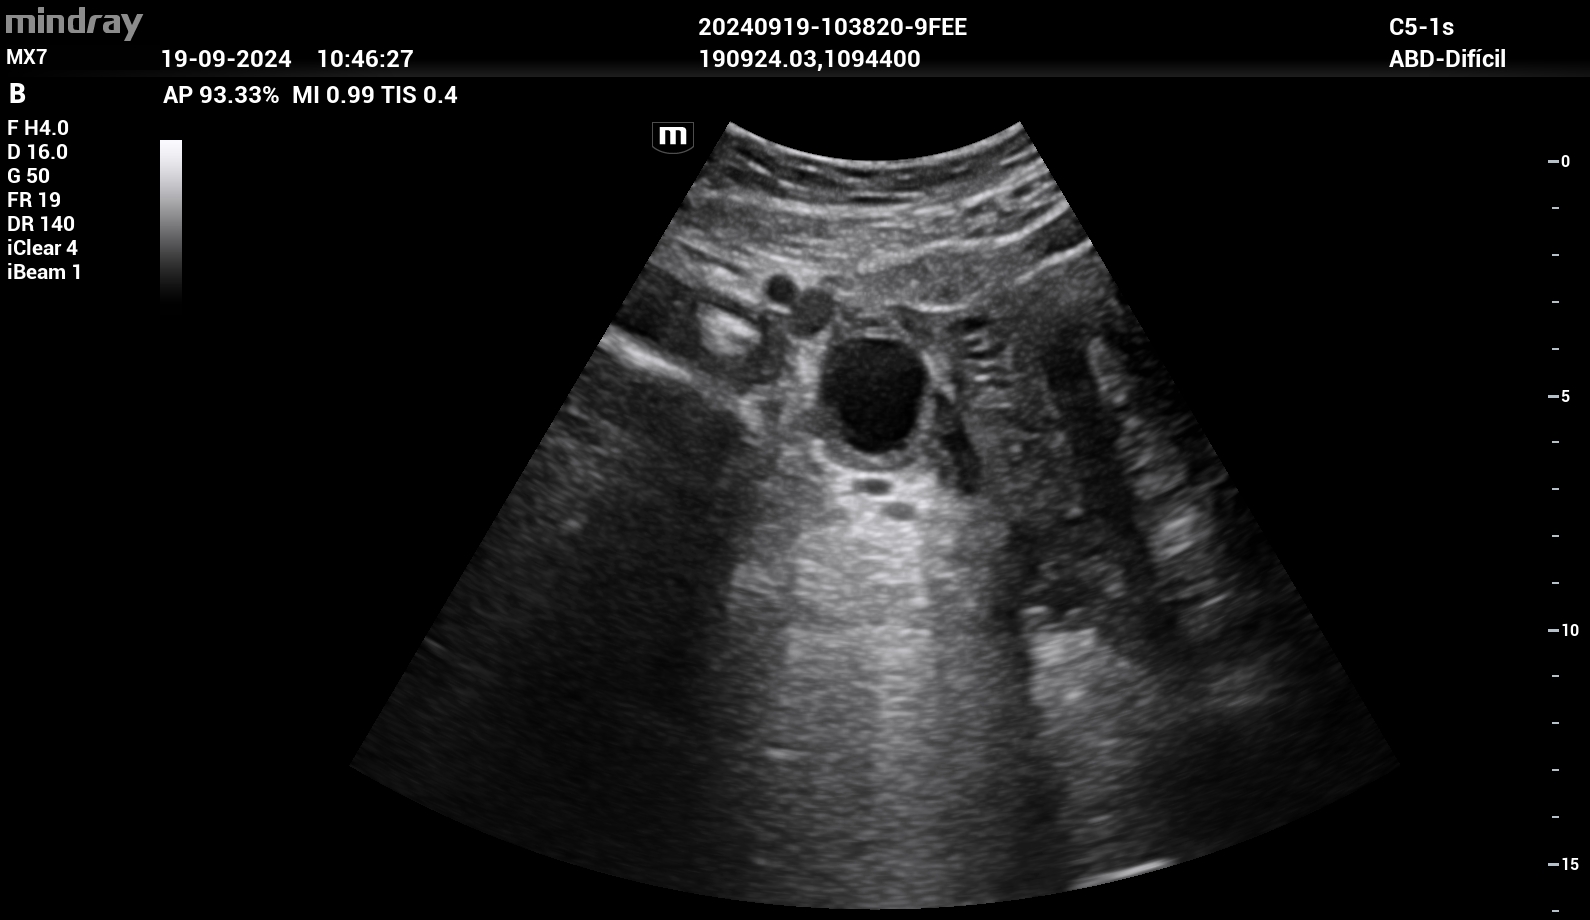

Se realizó ecografía clínica donde se objetivó líquido libre intraabdominal en espacio de Douglas. Útero en anteversión sin vesícula gestacional en interior. En región paraovárica derecha presentaba imagen ecomixta de 40 x 31 mm sugestiva de embarazo ectópico.